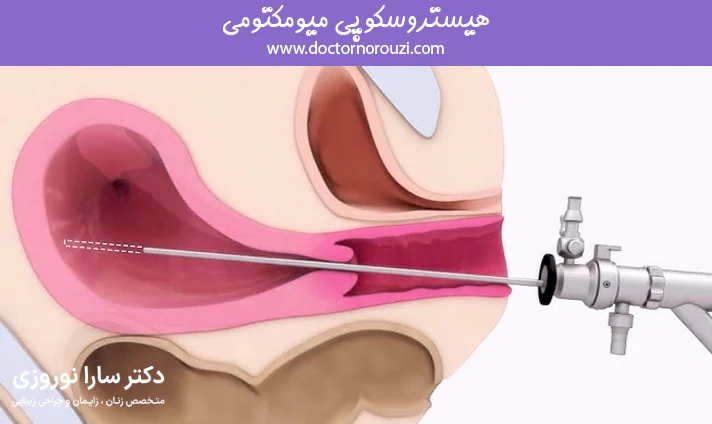

هیستروسکوپی میومکتومی یکی از روشهای کمتهاجمی و موثر برای درمان فیبرومهای رحمی (میومها) است که با استفاده از یک دستگاه نازک و دوربیندار به نام هیستروسکوپ از طریق واژن و دهانه رحم انجام میشود. این روش با هدف برداشتن فیبرومهایی که داخل حفره رحم رشد کردهاند، به ویژه در زنانی که دچار خونریزیهای غیرطبیعی، ناباروری یا دردهای لگنی هستند، کاربرد دارد و بدون نیاز به برش شکم انجام میگیرد. در این مقاله به بررسی کامل این روش، مزایا، مراحل انجام و مراقبتهای پس از آن میپردازیم.

هیستروسکوپی میومکتومی یک روش پیشرفته و غیرتهاجمی برای برداشت فیبرومهای داخل رحمی است که با کمک دستگاهی باریک و دوربیندار از طریق واژن و دهانه رحم انجام میشود. در این روش جراح بدون نیاز به برش خارجی، مستقیما به داخل رحم دسترسی پیدا میکند و فیبرومهای مزاحم را با دقت بالا خارج مینماید. این عمل معمولا با بیحسی موضعی یا بیهوشی سبک انجام میشود و دوره نقاهت کوتاهی دارد. هیستروسکوپی میومکتومی گزینهای مناسب برای زنانی است که قصد حفظ رحم دارند یا بهدنبال درمان ناباروری، خونریزی غیرطبیعی یا دردهای رحمی هستند.

جراحی فیبروم با روش هیستروسکوپی، یک عمل کمتهاجمی است که از طریق واژن و بدون نیاز به ایجاد برش در شکم انجام میشود. در این روش، پزشک یک ابزار نازک و لولهای شکل به نام هیستروسکوپ را از طریق دهانه رحم وارد حفره رحم میکند. این دستگاه مجهز به دوربین و منبع نور است و تصاویر واضحی از داخل رحم را روی مانیتور نمایش میدهد.

هنگامی که فیبروم (میوم) شناسایی شد، ابزارهای مخصوص از داخل هیستروسکوپ عبور داده میشوند تا فیبرومها را بهدقت برش دهند و خارج کنند. این عمل معمولاً برای فیبرومهای زیرمخاطی یا آنهایی که داخل حفره رحم رشد کردهاند، مناسب است.

در بیشتر موارد، هیستروسکوپی میومکتومی با بیحسی موضعی یا بیهوشی سبک انجام میشود و زمان جراحی بین ۳۰ تا ۶۰ دقیقه طول میکشد. بیمار معمولاً همان روز مرخص میشود و دوره بهبودی کوتاهی را تجربه میکند. این روش به دلیل دقت بالا، کمترین میزان عارضه و حفظ سلامت رحم، گزینهای ایدهآل برای زنانی است که قصد بارداری دارند یا به دنبال جراحی غیرتهاجمی هستند.